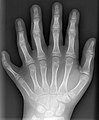

-

Historische Aufnahme einer Hand mit Ring (Röntgen, 23. Januar 1896) -

Eine moderne Aufnahme einer linken Hand mit 6 Fingern (Polydaktylie) -